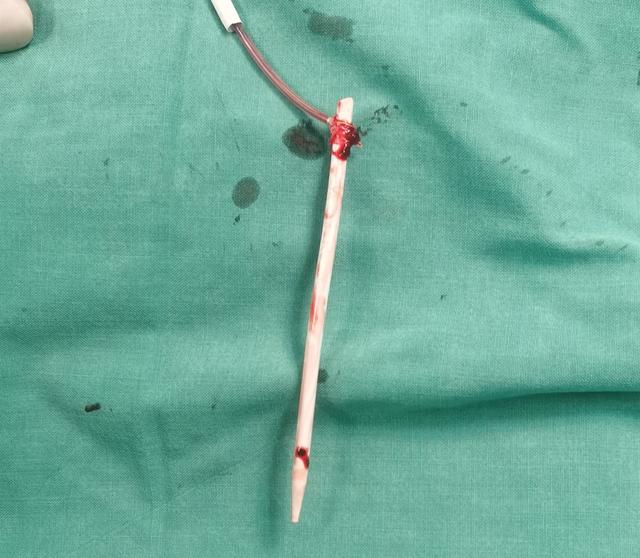

经过术前反复商讨 , 欧阳尚副主任医师等制定了详细的手术方案 。 术中 , 采用超声引导穿刺右侧大隐静脉近段 , 圈套器反复尝试套取透析管 , 但由于管子两头均顶壁 , 费了好一番功夫才“钓鱼”成功 。 因透析管太粗无法收入血管鞘 , 于是顺着血管将其拽入股静脉 , 采用神奇的“托马斯回旋” , 将透析管拖入表浅的大隐静脉 , 这样管子就可在皮下触及 。 剩下的事情就很简单 , 在皮肤表面切个小口子 , 直接就能看到大隐静脉和透析管 , 稍微用力就将管子取了出来 。 事后测量 , 取出的透析管长约113mm 。